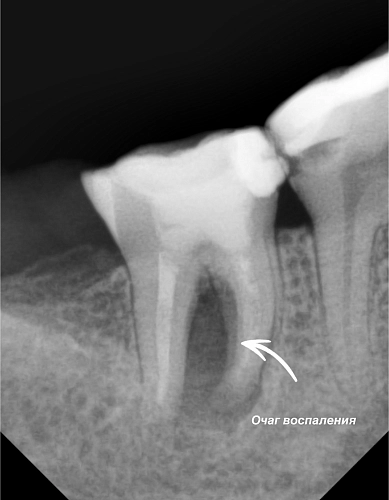

Сегодня расскажем о работе Морозовой Александры Сергеевны, которая смогла вернуть к жизни зуб, казалось бы, безнадежный. Пациент обратился к нам после консультации в другой клинике, где ему рекомендовали удалить инфицированный зуб. После тщательной диагностики по результатам компьютерной томографии, прицельным рентгенографияческим снимками и диагностическому препарированию под микроскопом, было решено зуб сохранять. Проведенное лечение корневых каналов под большим увеличением позволило тщательно и качественно очистить пораженные участки. После этого было выполнено пломбирование, и зуб был восстановлен и подготовлен под временную коронку для дальнейшего наблюдения.